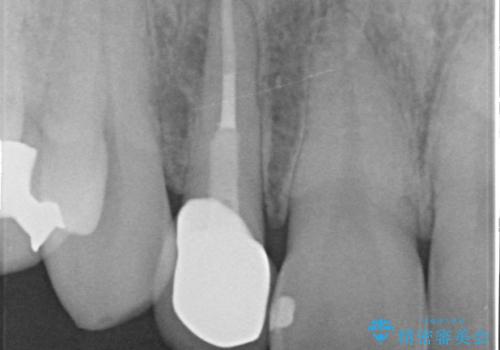

- 金属を使っていない被せ物に替えたいといらっしゃった方の症例です。

再根管治療終了後、オールセラミッククラウンによる補綴を行いました。

- オールセラミッククラウン(スペシャル)…¥130,000、仮歯…¥10,000、ファイバーコア…¥20,000、精密根管治療費別途費用は治療当時の料金となります

今回用いたオールセラミッククラウンはジルコニアフレームという白い素材の上にセラミックを盛っているため、審美性が非常に高いのが特徴です。

また、ジルコニアは人工ダイヤモンドの材料にも使われているほど高い強度を持っており、そのためオールセラミッククラウンは審美性だけでなく、奥歯やブリッジの補綴も可能とするクラウンです。